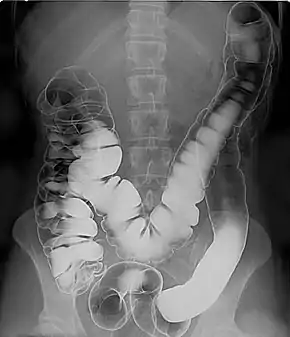

Air

Barium sulfate is mainly used in the imaging of the digestive system. The substance exists as a water-insoluble white powder that is made into a slurry with water and administered directly into the gastrointestinal tract.

- Barium enema (large bowel investigation) and DCBE (double contrast barium enema)

Barium sulfate, an insoluble white powder, is typically used for enhancing contrast in the GI tract. Depending on how it is to be administered the compound is mixed with water, thickeners, de-clumping agents, and flavourings to make the contrast agent. As the barium sulfate doesn't dissolve, this type of contrast agent is an opaque white mixture. It is only used in the digestive tract; it is usually swallowed or administered as an enema. After the examination, it leaves the body with the feces.